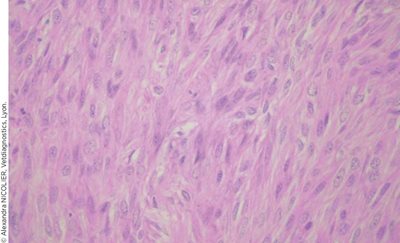

L’analyse histopathologique conclut à un léïomyosarcome ovarien pour les trois furettes (Photo 4).

Photo 4 : Vue microscopique (HE, grossissement x 40) d’une coupe histologique d’une masse montrant une tumeur mésenchymateuse.

L’anisocytose et l’anisocaryose sont modérées et quelques atypies sont observées. Les mitoses sont peu nombreuses.